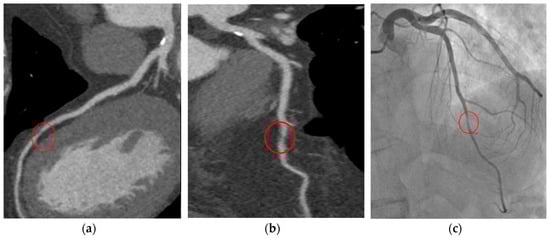

6.1. FFR-CT

- Pontone, G. Anatomy and physiology in ischaemic heart disease: A second honeymoon? Eur. Heart J. 2016, 37, 1228–1231. [Google Scholar] [CrossRef]

- Taylor, C.A.; Fonte, T.A.; Min, J.K. Computational fluid dynamics applied to cardiac computed tomography for noninvasive quantification of fractional flow reserve: Scientific basis. J. Am. Coll. Cardiol. 2013, 61, 2233–2241. [Google Scholar] [CrossRef] [PubMed]

- Ball, C.; Pontone, G.; Rabbat, M. Fractional Flow Reserve Derived from Coronary Computed Tomography Angiography Datasets: The Next Frontier in Noninvasive Assessment of Coronary Artery Disease. BioMed Res. Int. 2018, 2018, 2680430. [Google Scholar] [CrossRef]

- Pontone, G.; Muscogiuri, G.; Andreini, D.; Guaricci, A.I.; Guglielmo, M.; Mushtaq, S.; Baggiano, A.; Conte, E.; Beltrama, V.; Annoni, A.; et al. The New Frontier of Cardiac Computed Tomography Angiography: Fractional Flow Reserve and Stress Myocardial Perfusion. Curr. Treat. Options Cardiovasc. Med. 2016, 18, 74. [Google Scholar] [CrossRef]